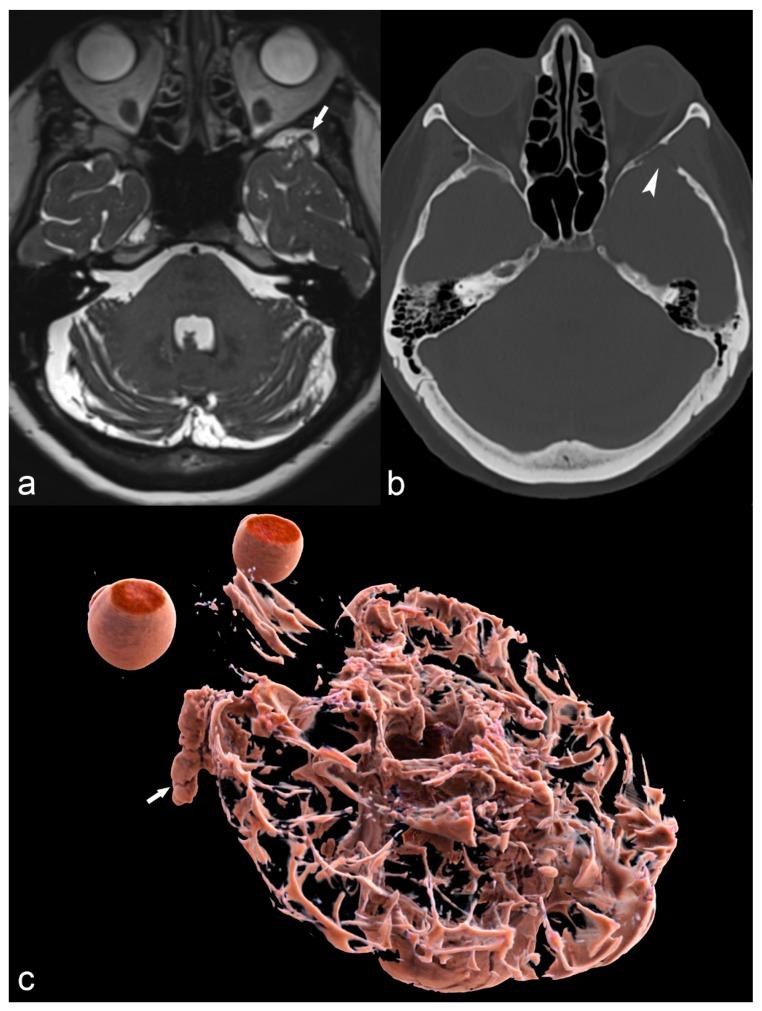

The etiology of epilepsy is variable and sometimes multifactorial. Clinical course and response to treatment largely depend on the precise etiology of the seizures. Along with the electroencephalogram (EEG), neuroimaging techniques, in particular, magnetic resonance imaging (MRI), are the most important tools for determining the possible etiology of epilepsy. Over the last few years, there have been many developments in data acquisition and analysis for both morphological and functional neuroimaging of people suffering from this condition. These innovations have increased the detection of underlying structural pathologies, which have till recently been classified as "cryptogenic" epilepsy. Cryptogenic epilepsy is often refractory to anti-epileptic drug treatment. In drug-resistant patients with structural or consistent functional lesions related to the epilepsy syndrome, surgery is the only treatment that can offer a seizure-free outcome. The pre-operative detection of the underlying structural condition increases the odds of successful surgical treatment of pharmacoresistant epilepsy. This article provides a comprehensive overview of neuroimaging techniques in epilepsy, highlighting recent advances and innovations and summarizes frequent etiologies of epilepsy in order to improve the diagnosis and management of patients suffering from seizures, especially young patients and children.